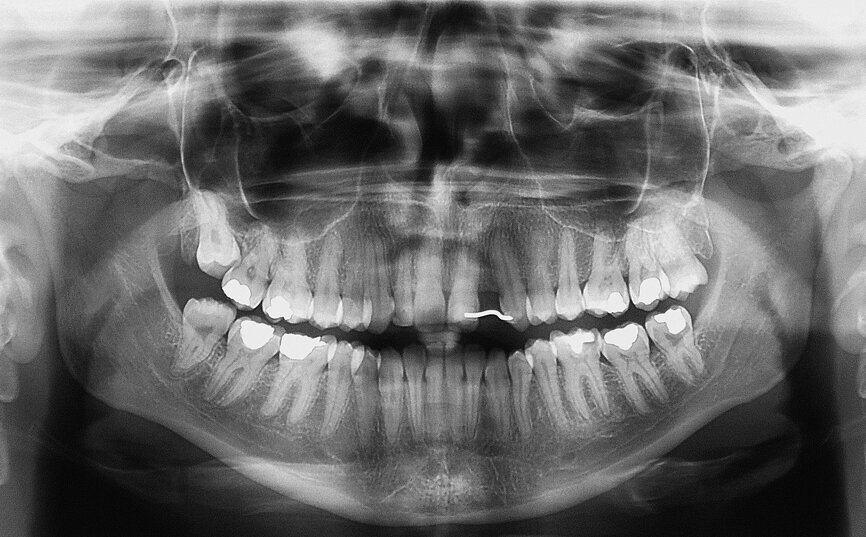

Fig. 1 : Radiographie panoramique. Il faut noter l’espace restreint en position de la dent 22.